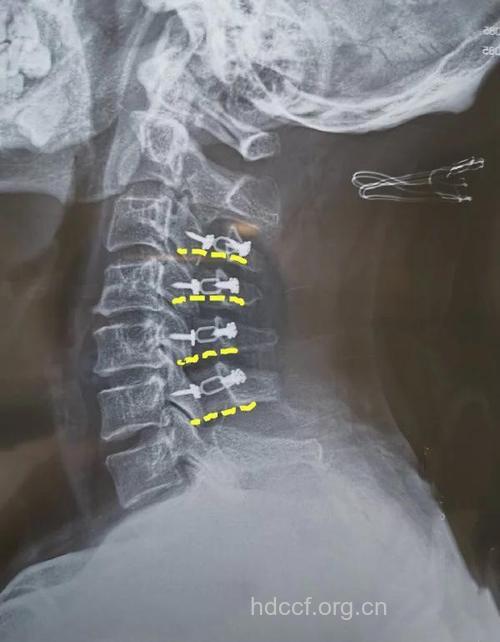

脊髓型颈椎病,因颈椎间盘突出或后纵韧带骨化等压迫脊髓,一旦出现持物不稳、系扣不灵活,肢体无力、行走不稳等情况,也应尽早手术。

颈椎病手术的主要目的是挽救脊髓功能,不仅只是为了提高生活质量。脊髓神经元细胞变性以后,再恢复的可能性几乎为零。对于脊髓受压比较严重的患者,在日常生活中受到轻微的头颈部外伤就可能引起肢体瘫痪,再急诊手术效果也不会太理想,术后恢复程度非人力所能掌控。